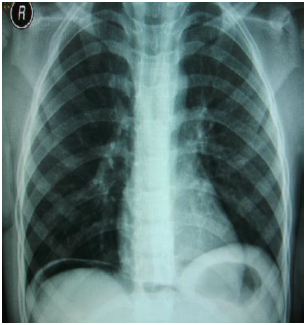

Paciente do sexo masculino, 47 anos, refere que, há mais ou menos 12 horas, iniciou com quadro de dor abdominal lancinante, súbita, intensidade 9/10, de localização epigástrica, e posterior irradiação para todo o abdome, contínua, sem fatores atenuantes, acompanhada de vômitos escuros e com restos alimentares. Tem dor abdominal crônica, nega doenças cardíacas, hipertensão e diabetes. Ao exame, encontrava-se lúcido, pálido, desidratado, facies álgica, sudorético, taquipneico, tempo de enchimento capilar lentificado, abdome difusamente doloroso com tensão aumentada, timpanismo difuso, peristalse ausente, cicatriz umbilical protusa. Sinais vitais: FC 126 bpm, PA 80/60 mmhg, FR 36irpm, Sat 85%. O paciente veio de outro município com este rx em mãos.

Com base na história clínica e nos achados do exame físico e de imagens desse paciente, responda aos itens a seguir:

1) Qual o diagnóstico sindrômico?

2) Você solicitaria mais exames de imagem para elucidação desse caso específico? Em caso afirmativo, cite quais seriam.

3) Qual o dado no exame físico é essencial para elucidação do diagnóstico clínico? Explique o que ele significa.

4) Descreva qual alteração encontrada na radiografia em questão.

5) Qual deve ser a conduta médica imediata para esse caso?